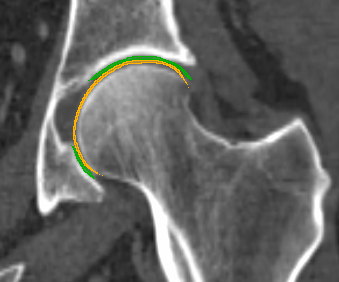

We have qualitatively verified that the articulating surfaces in all the ten HJs are detected correctly regardless of their anatomical variance using visual inspection of overlays as shown in Fig. 4. As desired, we observe a high degree of congruence between the opposing joint surfaces, meaning no gaps or overlaps in the cartilage-cartilage interface. Moreover, we observe a smooth transition towards the bone geometries as expected from the correct anatomy. The parameter values used to generate the cartilage from Fig. 5(a). The free parameters are the neighbourhood-size used to estimate the curvature of the bone (𝒩𝒩\mathcal{N}); the minimum and maximum curvature in the cartilage region (κmin,κmaxsubscript𝜅subscript𝜅\kappa_{\min},\kappa_{\max}; Eq. (2)); the distance parameter in mm𝑚𝑚mm (δ𝛿\delta; Eq. 1); and the number of times the outer boundary should be trimmed (Ntrimsubscript𝑁𝑡𝑟𝑖𝑚N_{trim}). Here, the curvature based parameters (𝒩,κmin,κmax)\mathcal{N},\kappa_{\min},\kappa_{\max}) are only used for the femur. See supplementary material for more visual comparisons.

Refer to caption

(a) Von Mises stress.

(b) CT scan overlay.

Figure 4: The von Mises stress patterns ((a)) and the generated cartilage imposed on the CT scan from which the bone was extracted ((b)). Notice the high level of congruence in the cartilage-bone interfaces and cartilage-cartilage interface.